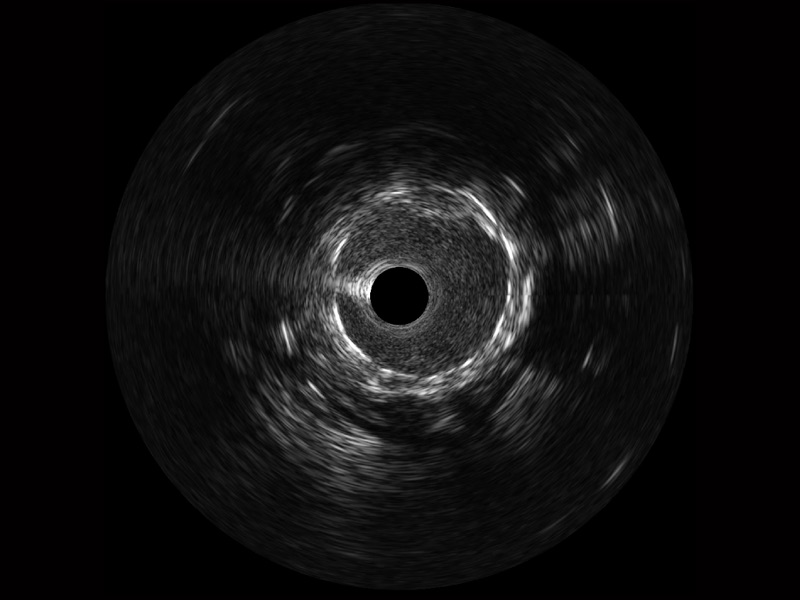

开立宽频IVUS图像

对比传统IVUS导管成像,开立宽频IVUS图像的近场支架梁显影更细腻,远场中膜外血管仍清晰可辨,兼顾远中近,兼顾分辨力与穿透深度